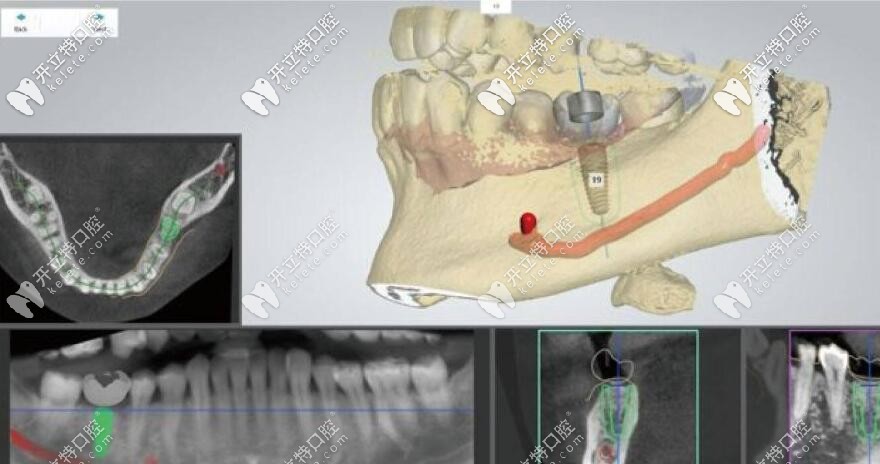

1、運用數(shù)字化3D導(dǎo)板技術(shù),制定種植方案:以微創(chuàng)為主導(dǎo),形成全頭顱360°影像;

2、通過CAD/CAM激光掃描和CBCT等,在計算機上重建患者口腔三維立體模型,有效掌握顧客的組織結(jié)構(gòu),清楚還原牙神經(jīng)和血管的位置。

3、由3D打印技術(shù)制作的種植導(dǎo)板,對手術(shù)全程的精準把控,設(shè)定種植位置能有效避開牙組織損傷和牙神經(jīng)位置,極大限度減少手術(shù)時間及手術(shù)創(chuàng)傷,實現(xiàn)手術(shù)方案。